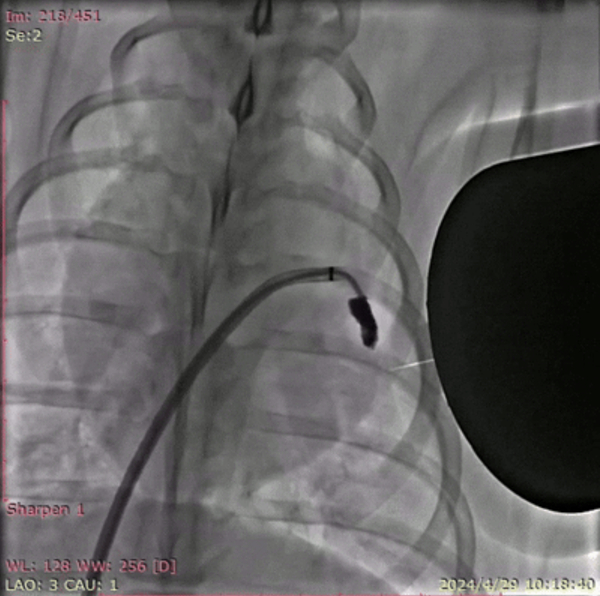

DSA(数字减影血管造影)拍摄的巴马猪体内磁流体左心耳封堵实验过程。深圳先进院供图

研究人员在8头巴马猪、30只SD大鼠,以及比格犬的跨物种验证中发现,该材料在实验动物介入手术中无明显出血和心率异常。3D重建显示,新型磁流体机器人能够彻底封堵左心耳血栓,适用于各种复杂形态的左心耳。磁流体机器人在猪模型上植入2至10个月后,固化后的磁凝胶表面可形成光滑完整的心内膜,解剖学显示,无器械相关性血栓形成和心肌损伤,为团队提出的磁流体封堵术的有效性和安全性提供了有力支撑。